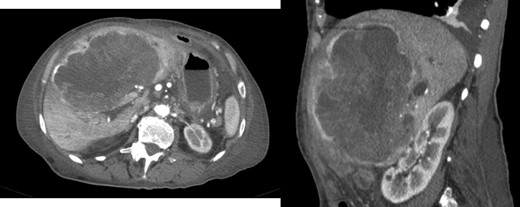

A 40-year-old woman with past medical history of c-section at the age of 26, was referred to our Hepatobiliary Unit in 2013, with diagnose of liver tumor with 16.6 cm (Fig. 2) suggestive of solitary fibrous tumor.

Abdominal Magnetic Resonance – heterogeneous liver mass in segment 4 with 16.6 cm.

No distant metastasis was identified.